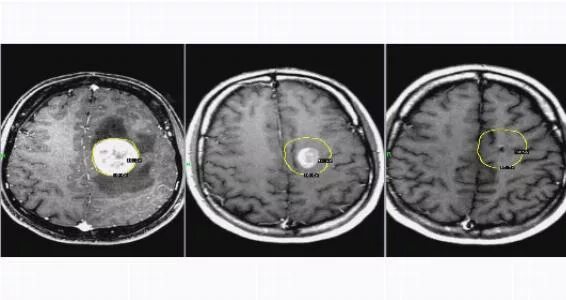

Отек головного мозга операции